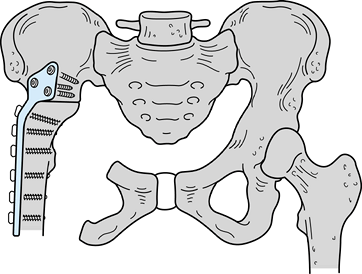

or both). The six-stage classification is as follows. (Fig. 126.21A illustrates the classifications, and Fig. 126.21B shows the distribution of 72 shoulder-girdle resections.)

![]() |

|

Figure 126.21. A: Classification of shoulder-girdle resections. B:

Distribution of 72 shoulder-girdle resections for bone tumors. (From Malawer MM, Meller I. A New Surgical Classification System for Shoulder Girdle Resection: Analysis of 38 Patients. Clin Orthop 1981;267:33, with permission.) |